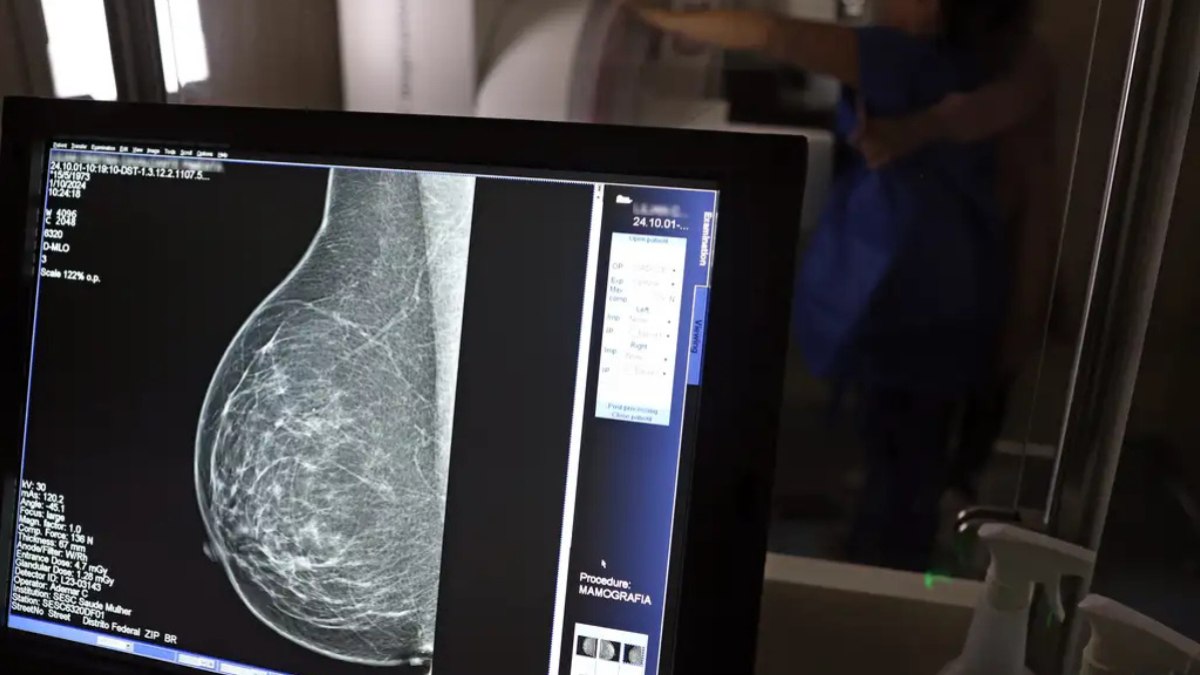

Mulheres entre 40 e 49 anos agora podem fazer mamografia pelo Sistema Único de Saúde (SUS) mesmo sem apresentar sinais de câncer de mama . A novidade foi anunciada pelo Ministério da Saúde na terça-feira (23).

Anteriormente o exame era recomendado para mulheres entre 50 e 69 anos e agora se estende para 40 a 74 anos .

Com a nova regra, a mamografia para mulheres de 40 a 49 anos pode ser feita quando houver necessidade, após a paciente e o profissional de saúde decidirem juntos.

O Ministério da Saúde explicou que, antes, mulheres nessa faixa etária tinham dificuldade para fazer o exame pelo SUS, pois precisavam ter histórico familiar ou sintomas. Mesmo assim, em 2024, mais de 1 milhão de mamografias foram realizadas em pacientes com menos de 50 anos, o que corresponde a 30% do total de exames feitos pelo SUS.